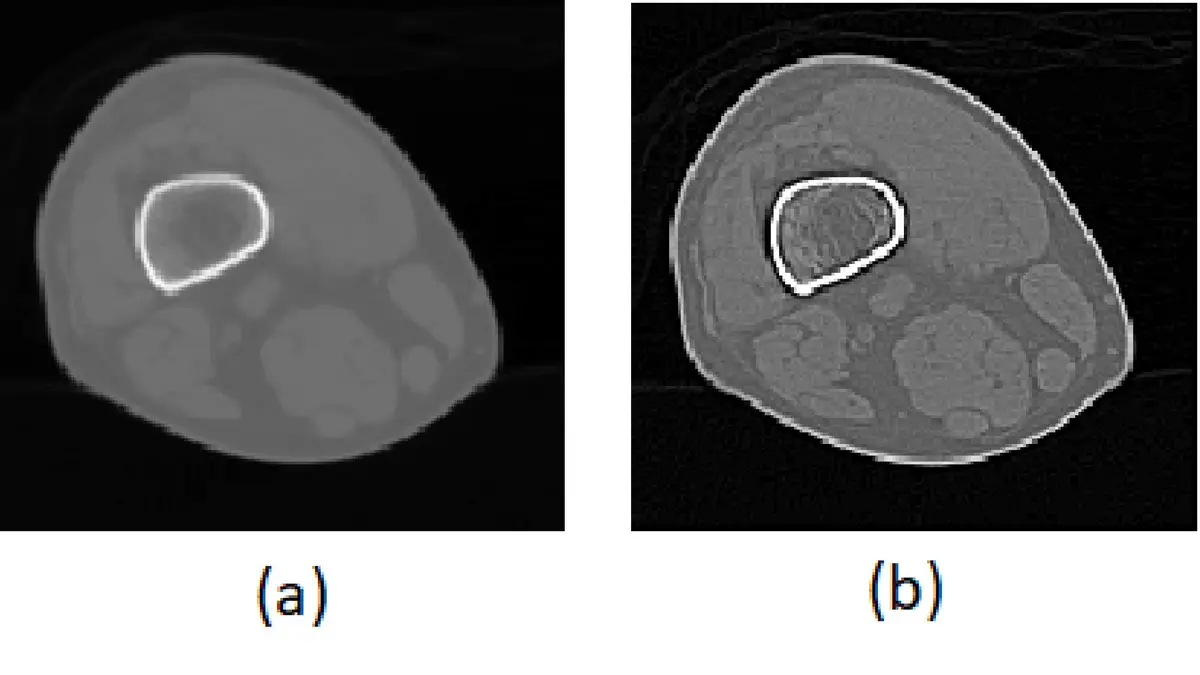

⼀數位影像原圖如圖 (a) ,經某影像處理後其結果如圖 (b) ,此影像銳化( image sharpening )是採⽤下列何種技術來模擬 Mach band effect (⾺赫帶效應)?

題目提供兩張對比影像(疑似四肢橫切面的 CT 影像):

- 圖 (a):原始影像,可見四肢軟組織橫切面,中央可見一骨性高密度(白色輪廓)結構,周圍軟組織輪廓模糊,整體影像邊緣不清晰,缺乏細節銳度。

- 圖 (b):經影像銳化處理後的結果,邊緣明顯加強,骨骼輪廓(白色邊緣)更為突出;更重要的是,各組織間的邊界出現了明顯的暗帶(dark band)與亮帶(bright band),這正是 Mach band effect 的典型表現。與原圖相比,軟組織的解剖細節(肌肉群、血管等)大幅清晰化,背景亦變得較暗(Laplacian 二階微分的結果),圖片整體呈現強烈邊緣強化效果。

這種邊緣周圍出現過衝(overshoot)暗-亮帶的影像,正是 Laplacian 二階微分加入原圖後的典型結果,視覺上模擬了人眼的 Mach band 感知。